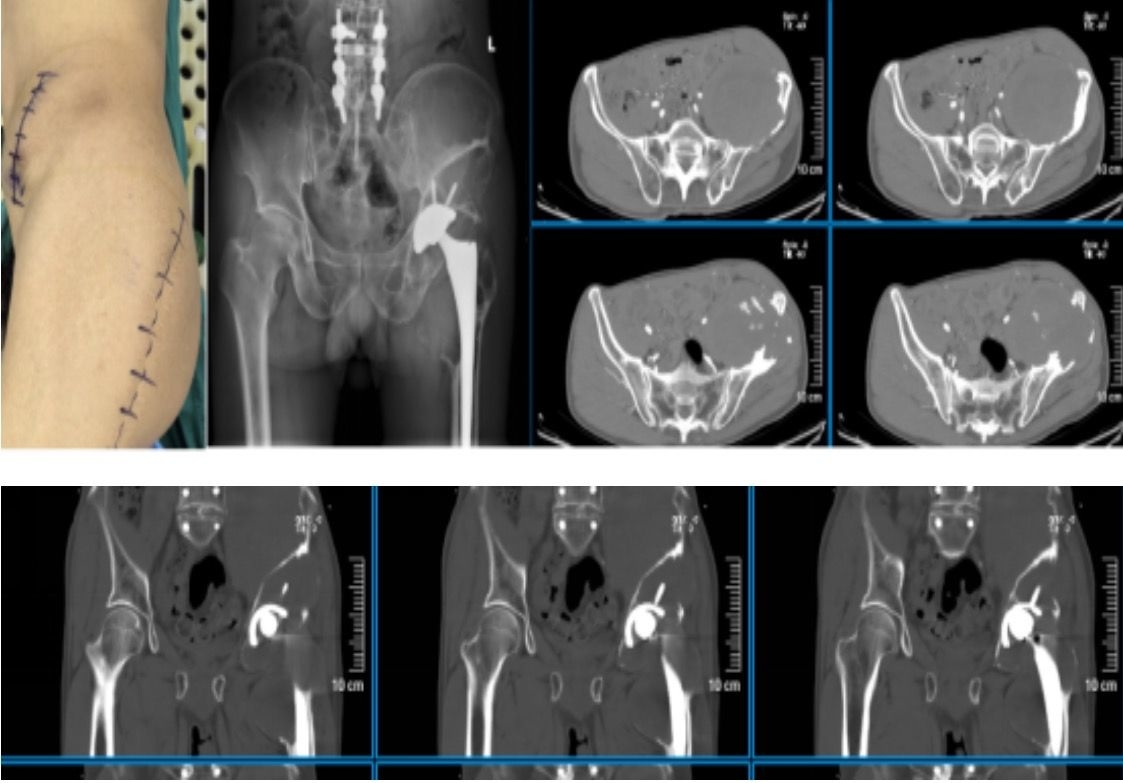

近日,四川大学华西医院骨科康鹏德主任医师团队成功为一名全髋关节置换术后25年、出现严重假体周围骨溶解合并髋关节周围及髂窝炎性巨大假瘤的患者完成高难度翻修手术。面对“骨盆几乎被掏空”的极端情况,术前经过周密设计并3D打印定制特殊假体,骨科、麻醉科、血管外科组成多学科团队,历经3小时奋战,最终实现假体稳定重建。术后第1天即扶助行器逐渐下地行走,术后第三日顺利出院。目前患者康复髋关节功能良好,在助行器辅助下患肢负重活动、功能康复。

经术前初步检查,提示患者的左髋臼假体松动,髋臼及股骨近段严重骨溶解、骨缺损,髋周及髂窝形成巨大炎性假瘤;盆腔CT血管造影,提示左侧髂动静脉与巨大的炎性假瘤关系密切,髂血管被炎性假瘤压迫并粘连。这意味着在清除骨溶解病灶、切除炎性假瘤的过程中有可能损伤盆腔动脉,引发术中大出血。

针对这一复杂病例,团队面临两大难题,第一是患者髋臼周围的炎性假瘤包块向上蔓延至髂窝,形成巨大软组织包块,且与髂血管紧密粘连,在分离、切除炎性假瘤的过程中出血风险极大,稍有不慎就可能损伤盆腔血管,手术视野受限,若止血不及时,将会威胁患者生命;第二是患者髋臼侧严重骨缺损,要如何重建原有髋关节的旋转中心,形成稳定固定。

针对髋臼骨缺损严重,目前的假体无法重建髋臼、无法获得稳定固定,团队拟采用3D打印技术定制特殊髋臼假体重建髋臼。

6月18日,由麻醉手术中心杨静主任医师团队麻醉,在手术室护理团队的精密配合下,康鹏德主任医师团队与胡瀚魁团队开展联合手术。术中通过仔细游离左侧髂动脉与髂窝炎性假瘤包块的粘连后,顺利完整切除病灶;同时通过后外侧入路实现了原有假体取出、骨溶解病灶清除及3D打印髋臼假体的精准植入。整个手术过程顺利,得益于麻醉科的平稳控制性降压及血管外科的辅助。